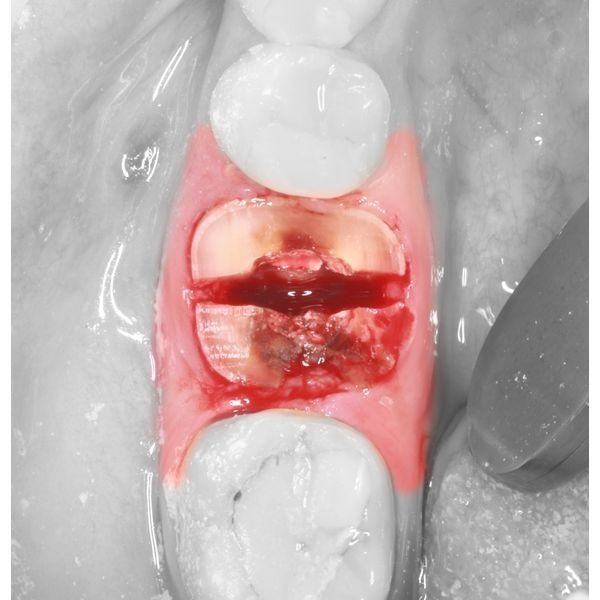

- сегменты извлекли элеватором и щипцами, после чего можно было увидеть широкую межкорневую перегородку костной ткани невооружённым глазом;

- в пустую лунку вставили модель зуба 2.8 из эпоксидной смолы, распечатанной на 3D-принтере (примерка показала, что зуб не до конца входит в лунку);

- углубили лунку с помощью твердосплавного шаровидного бора для механического наконечника, после чего модель встала на место;